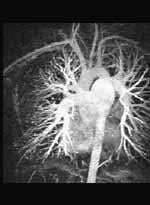

July 12, 2011 – To streamline diagnosis and enable greater overall exam efficiency, Toshiba America Medical Systems Inc. has announced U.S. Food and Drug Administration (FDA) approval of VirtualExplorer Version 3.1, a software upgrade package for Toshiba Magnetic Resonance (MR) VirtualExplorer workstations. The software provides enhanced post-processing functionality, and the new cardiac package includes MR flow analysis, which allows clinicians to measure flow and velocity when imaging the heart.

The software includes features such as 3-D image visualization, DICOM viewer, 2-D filming, double oblique and virtual endoscope. The cardiac edition of the software upgrade also includes features specific to cardiac imaging, such as MR flow analysis, MR cardiac analysis, MR coronary analysis and delayed enhancement. Additionally, the neuro edition of the software includes brain perfusion for neuro evaluation.